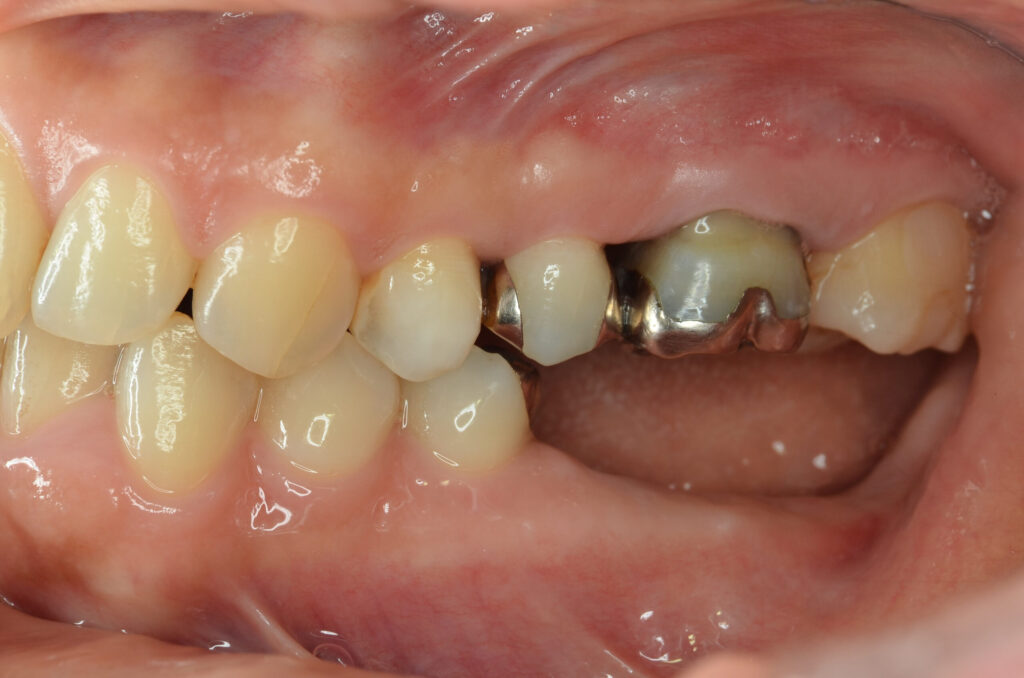

Before

After

治療内容

インプラント2本・骨造成併用

治療期間・回数

約4ヶ月・約4回

費用

880,000円

治療のリスク

外科手術が必要になるため、患者様に体力的な負担がかかる。